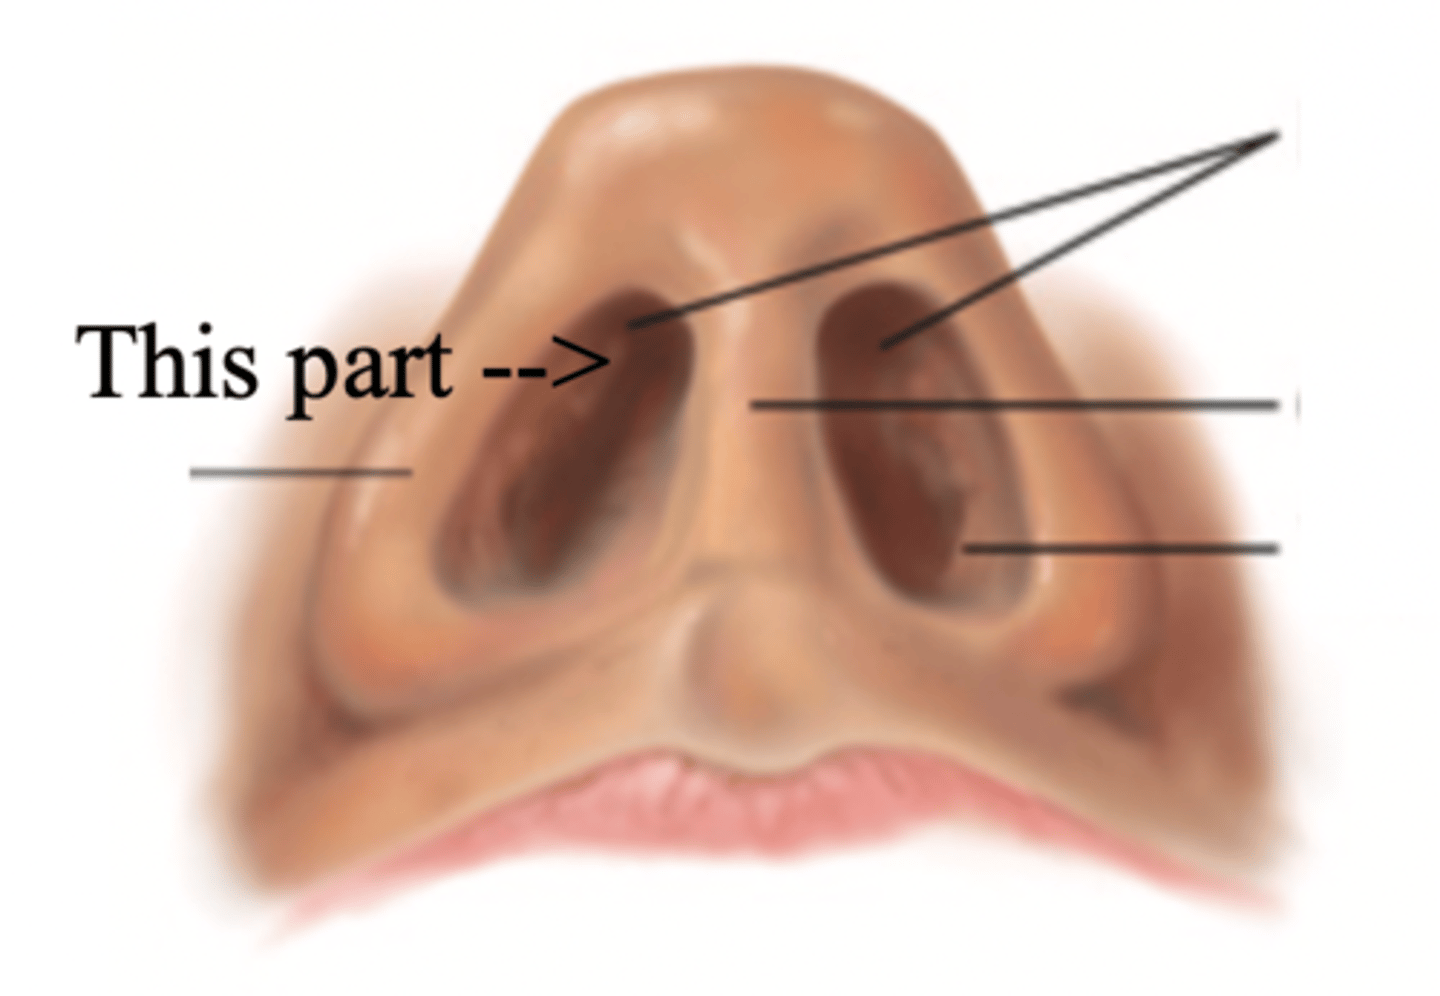

Nose

Organ of smell

Bridge

Tip

Ala

Nares

Columella

Vestibule